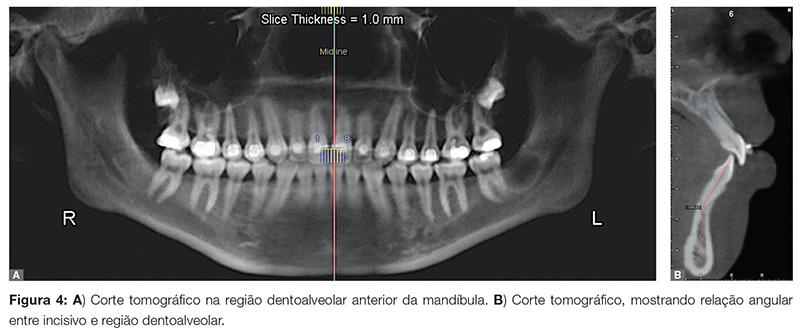

Na Figura 3, nota-se o ângulo dos incisivos inferiores medido em uma cefalometria convencional. Ao realizarmos cortes 3D a partir de uma tomografia, pode-se identificar com maior facilidade o grau de discrepância e inclinação de cada dente em relação à sua base alveolar (Fig. 4). Um maior grau de precisão em termos de direcionamento e movimentação dos dentes em questão pode ser planejado e obtido com a mecânica correta.

Em nosso prática clínica, dados obtidos rotineiramente em análises cefalométricas 2D são confirmados em detalhes e personalizados por regiões com o uso de imagens 3D obtidas a partir de tomografias do tipo cone beam. A inclinação de incisivos superiores e inferiores é um exemplo típico. Normalmente medidos por ângulos como o IMPA, o uso de imagens 3D e de softwares de visualização dessas imagens nos permite personalizar a inclinação dos dentes em relação à sua base óssea, e não a uma sobreposição de imagens.